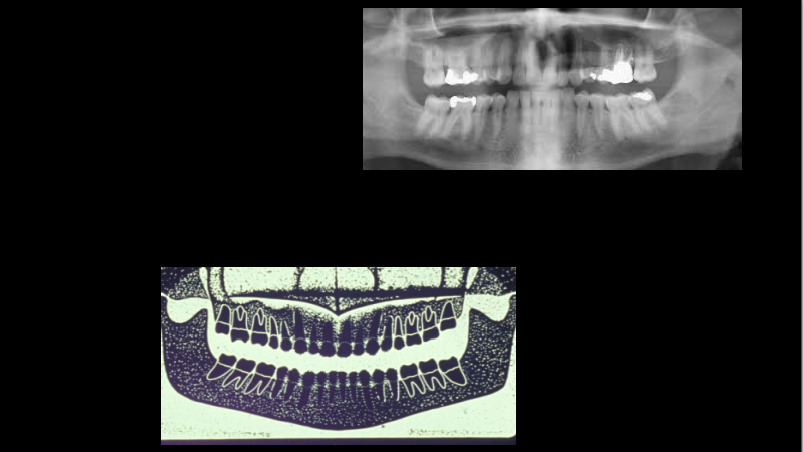

Name the errors

Palatoglossal space

earring ghost image